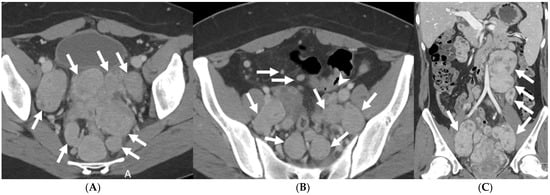

5.3.1. Disseminated Peritoneal Leiomyomatosis

5.3.2. Peritoneal Carcinomatosis

5.3.3. Peritoneal Tuberculosis